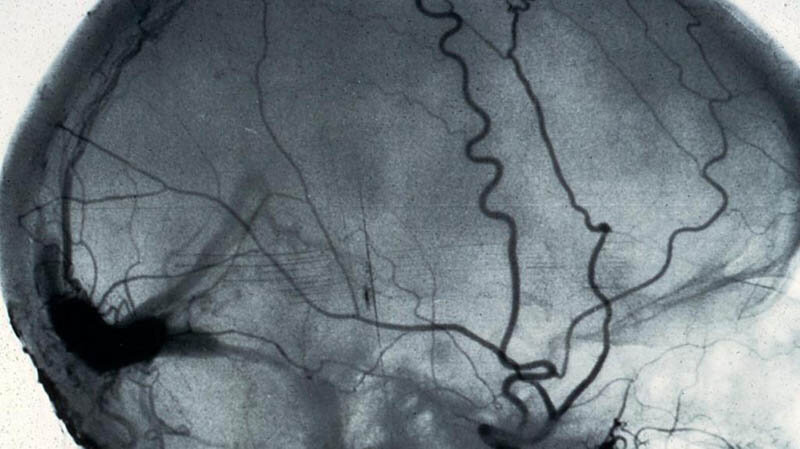

Ангиография представляет собой метод исследования, при котором в просвет сосуда вводится специальный контрастный препарат и производится рентгеновский снимок. Ангиографическое исследование позволяет врачу выявить и наметить пути лечения заболеваний сосудов. Суть метода состоит в том, что через небольшой разрез на коже в области паха или на запястье под местной анестезией в просвет артерии вводится специальный пластиковый гибкий катетер. Статья содержит следующие разделы: · Как пациенту необходимо готовиться к ангиографии? · Какие анализы и исследования необходимы для госпитализации · Что происходит после ангиографии · Цены на ангиографию Читать полную статью на сайте клиники >>>

Ангиография представляет собой метод исследования, при котором в просвет сосуда вводится специальный контрастный препарат и производится рентгеновский снимок. Ангиографическое исследование позволяет врачу выявить и наметить пути лечения заболеваний сосудов.

Суть метода состоит в том, что через небольшой разрез на коже в области паха или на запястье под местной анестезией в просвет артерии вводится специальный пластиковый гибкий катетер.